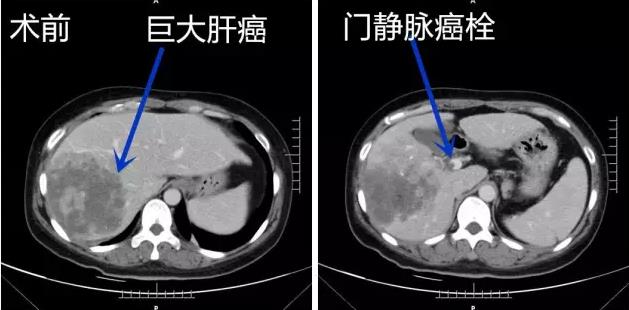

李晓勇教授及主管医生郜宇医师热情接待了王女士及其家人。在详细询问病史,全面评估病情,结合患者病史及CT检查结果后,李晓勇教授考虑患者为肝脏巨大恶性肿瘤(大小约120mm×110mm×105mm),与肝内重要血管(门静脉主支及右干、肝中静脉)关系密切,且存在门静脉右支癌栓形成,波及到门静脉左支(图一)。

图一